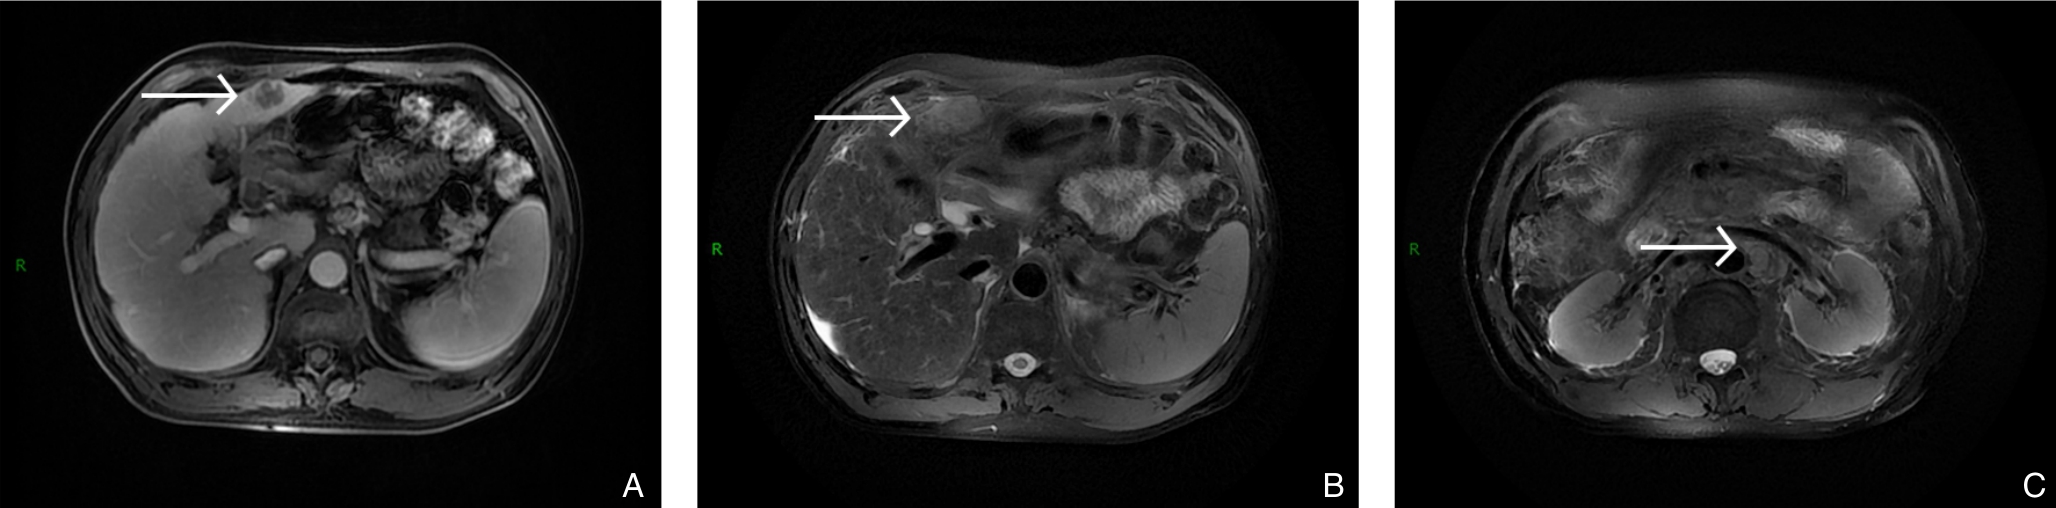

颜可梁,麦伟恒,康钟杰,刘春甫,李作标,刘晓光,陈卫煌,杨永光

2025, 34(8):1783-1789. doi: 10.7659/j.issn.1005-6947.250076

摘要:背景与目的 肝内胆管癌(ICC)是一种起病隐匿、预后极差、初诊多为进展期的原发性肝癌,其治疗选择有限,预后差。本研究旨在探讨靶向治疗、免疫治疗与肝动脉灌注化疗(HAIC)联合应用于晚期ICC的转化治疗的潜力,为临床转化治疗提供参考。方法 回顾广东医科大学附属医院2021年11月收治的1例晚期ICC行靶向治疗、免疫治疗与HAIC联合治疗后成功转化并接受手术患者的诊治过程,并复习国内外相关文献。结果 患者为52岁男性,确诊为T2N1M0-Ⅲb期ICC。患者拒绝接受以吉西他滨联合顺铂为主的一线化疗方案,同意行靶向治疗联合免疫治疗与HAIC的综合治疗,在接受4个治疗周期后评估肿瘤达到部分缓解,具备实施根治性手术治疗的条件。患者随后接受了腹腔镜下肝S6段和部分S7段切除、胆囊切除以及肝门部和腹膜后淋巴结清扫术。术后患者规律行靶向免疫联合化疗的综合治疗方案。在疾病出现复发和转移后,化疗药物进行了相应调整。截至目前,患者无病生存期达15个月,总生存期超过3年。结论 靶向治疗、免疫治疗与HAIC三联方案可提高晚期ICC患者的转化机会并延长生存期,具有较好的安全性和临床应用前景,但其疗效仍需多中心研究进一步验证。